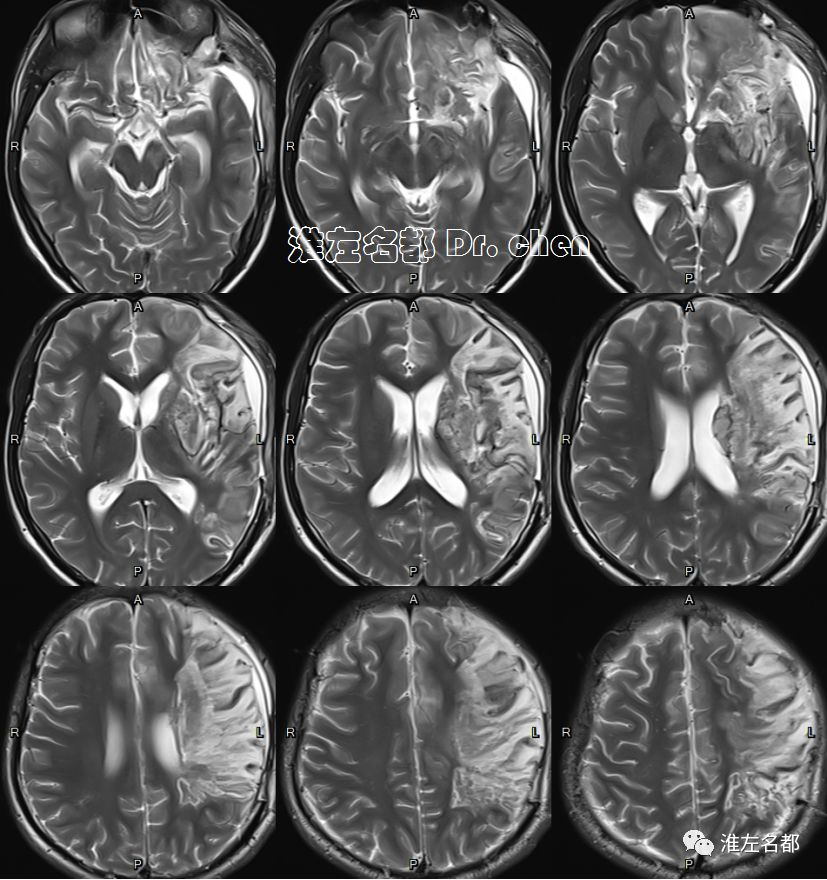

△T2WI、T1WI、FLAIR和SWI:左侧半球大面积亚急性梗死伴渗血,局部软化坏死。

△3D-TOF-MRA:左侧大脑中动脉M1段和前动脉A1段管腔显影不规则;左侧大脑中动脉分支显影较对侧稀疏(考虑和大面积梗死后供血需求降低有关)。

△管壁高分辨MRI(增强T1-SPACE):左侧大脑中动脉主干管壁未见异常(橙箭),左侧颈内动脉远端管壁增厚和强化(红箭)。

△管壁高分辨MRI(增强T1-SPACE):左侧颈内动脉末端检测到夹层“内膜征”(橙箭)。